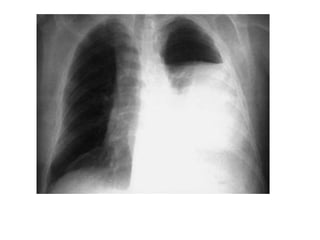

Derrame pleural tipico

neumotorax

hidroneumotorax